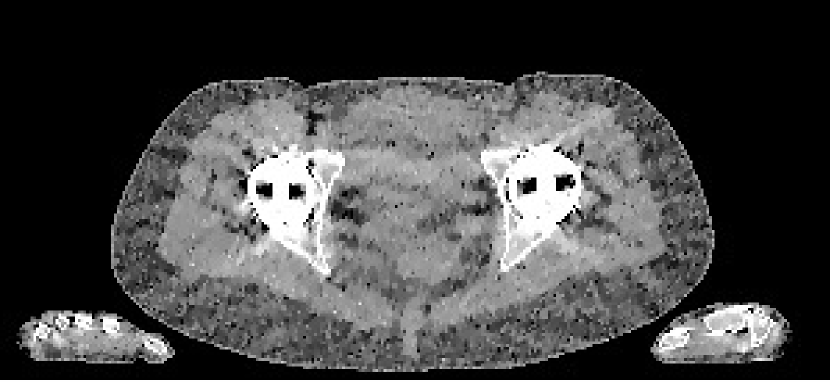

Figure 12: Metal insert visualisation of slice 91 from CBCT reconstructions with display window [0.7,1.4]. The Poly-SIR is the version based upon segmentation from the PWLS as that in Figure 11(c)

Reconstructions of the 83rd slice from the CBCT data are shown in Figure 11, along with a region from the 91st slice containing a higher mass of metal in Figure 12. Although the FBP appears to suffer strongly from the presence of the metal structure, most of the iterative methods mitigate its effect considerably, with the PWLS showing a more pronounce dark region in the soft tissue. The Poly-SIR based on a segmentation from the FBP does suffer from its streaking as shown in Figure 11(d). Although a better performance is achieved through segmenting from the PWLS as in Figure 11(d), this will have a considerably higher total computational cost; the Poly-SIR region in Figure 12(c) is based on this PWLS initialisation. The preservation of bone structure appears to be similar between all the iterative methods. The Polyquant method appears to have the smoothest regions around the metal implant, whilst maintaining the same level of structure in the bone and objects surrounding the phantom.

To evaluate the quantitative accuracy of each reconstruction, we isolated regions of interest (ROI) in the 83rd slice located in soft tissue and spongy bone — these are shown in Figure 11(a). The RMSE of these regions are calculated relative to the electron density of the soft tissue and bone equivalent resins, and shown in Table 4.

Table 4: Quantitative CBCT results: RMSE of relative electron density in regions shown in Figure 11(a)

RMSEFBPPWLSPoly-SIRIMPACTPolyquantROI 10.05830.01700.02000.01540.0100ROI 20.2310.02350.02560.01990.0166ROI 30.03420.03760.03330.01780.0128RMSEFBPPWLSPoly-SIRIMPACTPolyquantmissing-subexpressionmissing-subexpressionmissing-subexpressionmissing-subexpressionmissing-subexpressionmissing-subexpressionROI 10.05830.01700.02000.01540.0100ROI 20.2310.02350.02560.01990.0166ROI 30.03420.03760.03330.01780.0128\begin{array}[]{c|c|c|c|c|c}\text{RMSE}&\text{FBP}&\text{PWLS}&\text{Poly-SIR}&\text{IMPACT}&\text{Polyquant}\\ \hline\cr\text{ROI 1}&0.0583&0.0170&0.0200&0.0154&\mathbf{0.0100}\\ \text{ROI 2}&0.231&0.0235&0.0256&0.0199&\mathbf{0.0166}\\ \text{ROI 3}&0.0342&0.0376&0.0333&0.0178&\mathbf{0.0128}\\ \hline\cr\end{array}

From Table 4, we note that our proposed model is the most accurate method under test by at least 16% over other approaches in all regions.